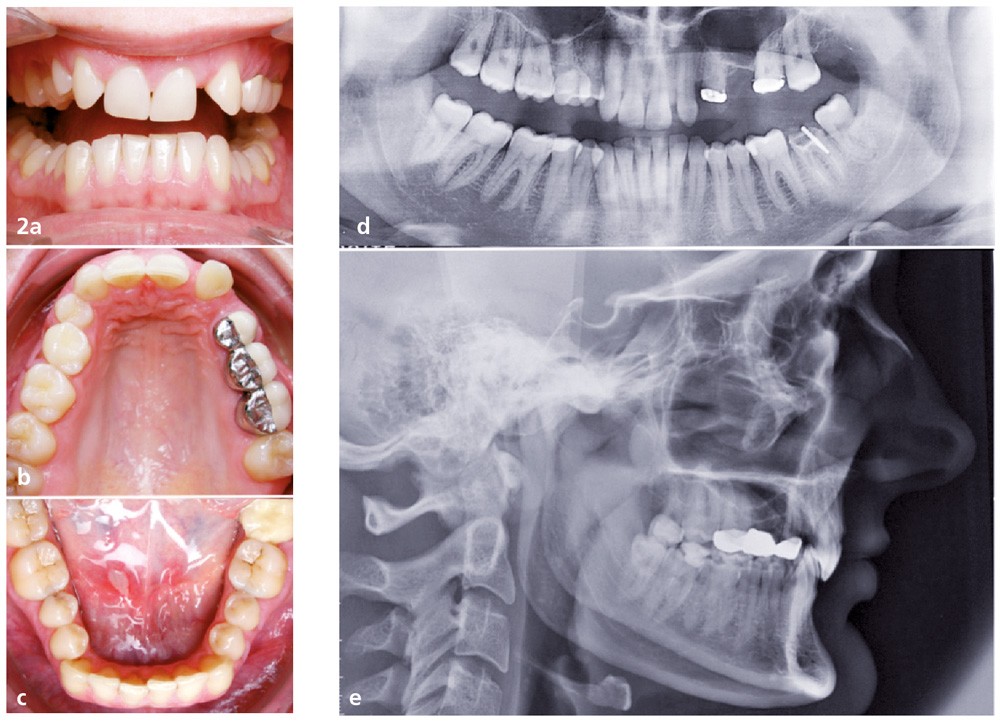

Les diagnostics sont très uniformes : classe II 2, schéma squelettique hypodivergent, bilan dentaire incomplet, quatre agénésies 1512 22 25 ; certains complètent avec l’asymétrie dans le plan frontal ou mandibulaire.

À la question « avez-vous déjà traité un cas identique ? », seules trois réponses sont positives. Les praticiens ont accepté de nous transmettre ces cas, mais nous n’en avons reçu que deux (le troisième est celui d’un jeune praticien qui ne l’a pas terminé). L’un des deux cas reçus est une classe III squelettique traitée sans chirurgie orthognatique et l’autre un cas de classe II 2 sévère sur un schéma squelettique classe II sévère. Dans les deux cas reçus, pas d’agénésie ni de…